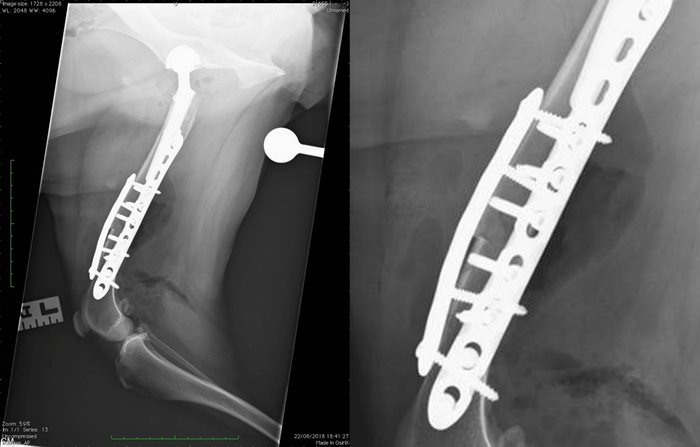

Revision surgery was performed (postoperative radiographs below) which involved replacement of the femoral head prosthesis and transverse osteotomy of the distal femoral diaphysis. The distal femur was internally rotated and stabilised to induce anteversion of the previously normoverted femoral prostheses.

The client returned to SCVS for re-examination approximately 16-weeks following surgery at SCVS, which involved a clinical examination and radiography. Radiographs (as seen below) demonstrated slow progression of healing of the femoral osteotomy with no implant-related complications. Palpation of the femoral osteotomy site was moderately resented. Based on these findings the primary clinician made the referral for ESWT to address delayed union of the femoral osteotomy, alongside a course of on-going physiotherapy and an on-lead exercise regimen.